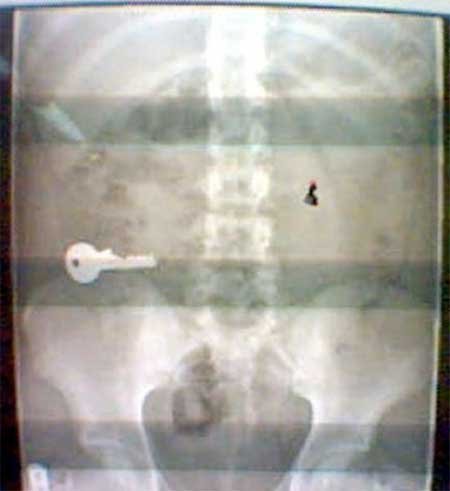

Một phụ nữ Trung Quốc đã nuốt 20 viên sỏi sau một vụ cãi nhau nảy lửa với bạn trai. Tình yêu có thể khiến bạn làm những việc nực cười.

Internet đầy những câu chuyện về người lớn lẫn trẻ nhỏ nuốt chìa khóa. Một sinh viên đang tham gia một bữa tiệc và uống hơi nhiều, khi bạn bè khăng khăng anh ta phải về nhà, sinh viên này nuốt luôn chìa khóa để có thể ở lại.